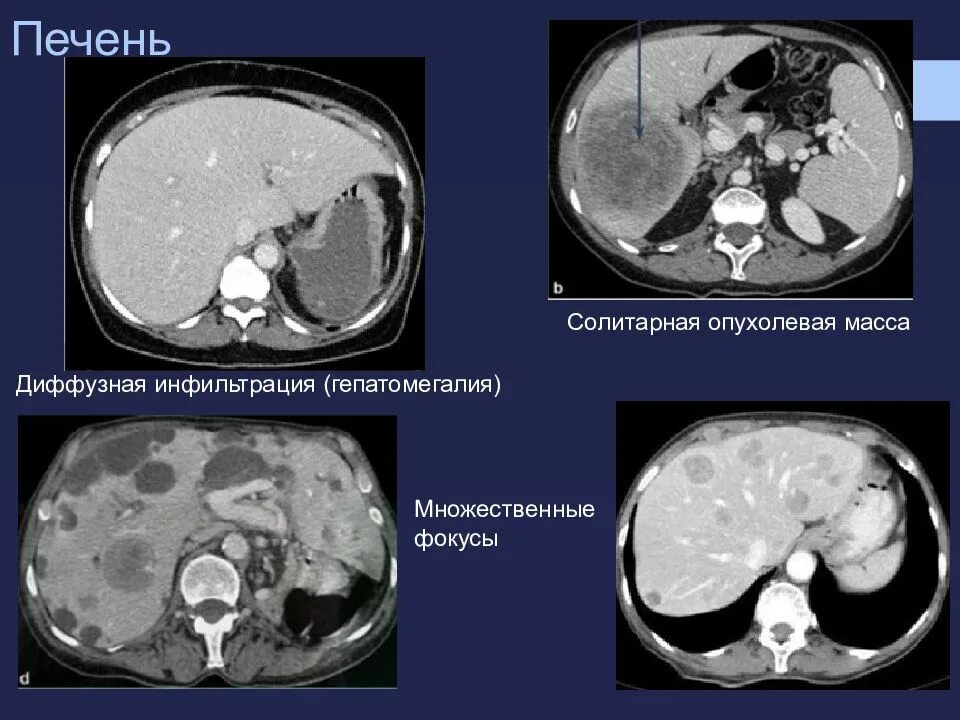

Диффузные изменения печени жировой гепатоз гепатомегалия